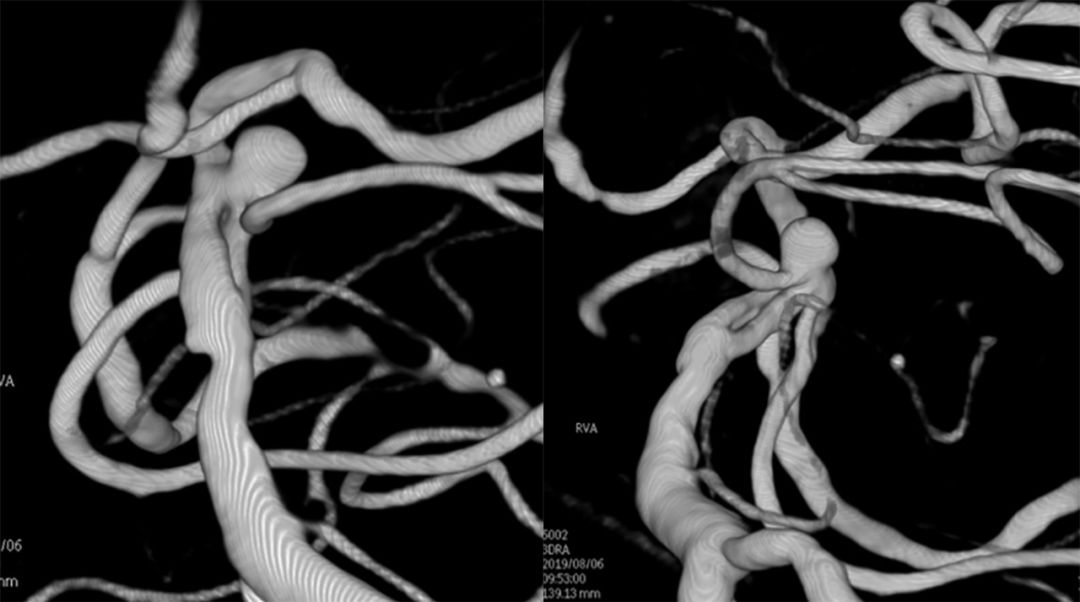

基底动脉进行三维血管重建:基底动脉有较粗和较细的2个管腔,左侧小脑上动脉瘤大小约2.3*2.1 mm(图9)。

图9

进行上述三次微量造影均可见双侧大脑后动脉显影,以及结合基底动脉三维重建图像,故判断基底动脉属于开窗,而非夹层。由于载瘤动脉较细,拟行单微管动脉瘤栓塞术。